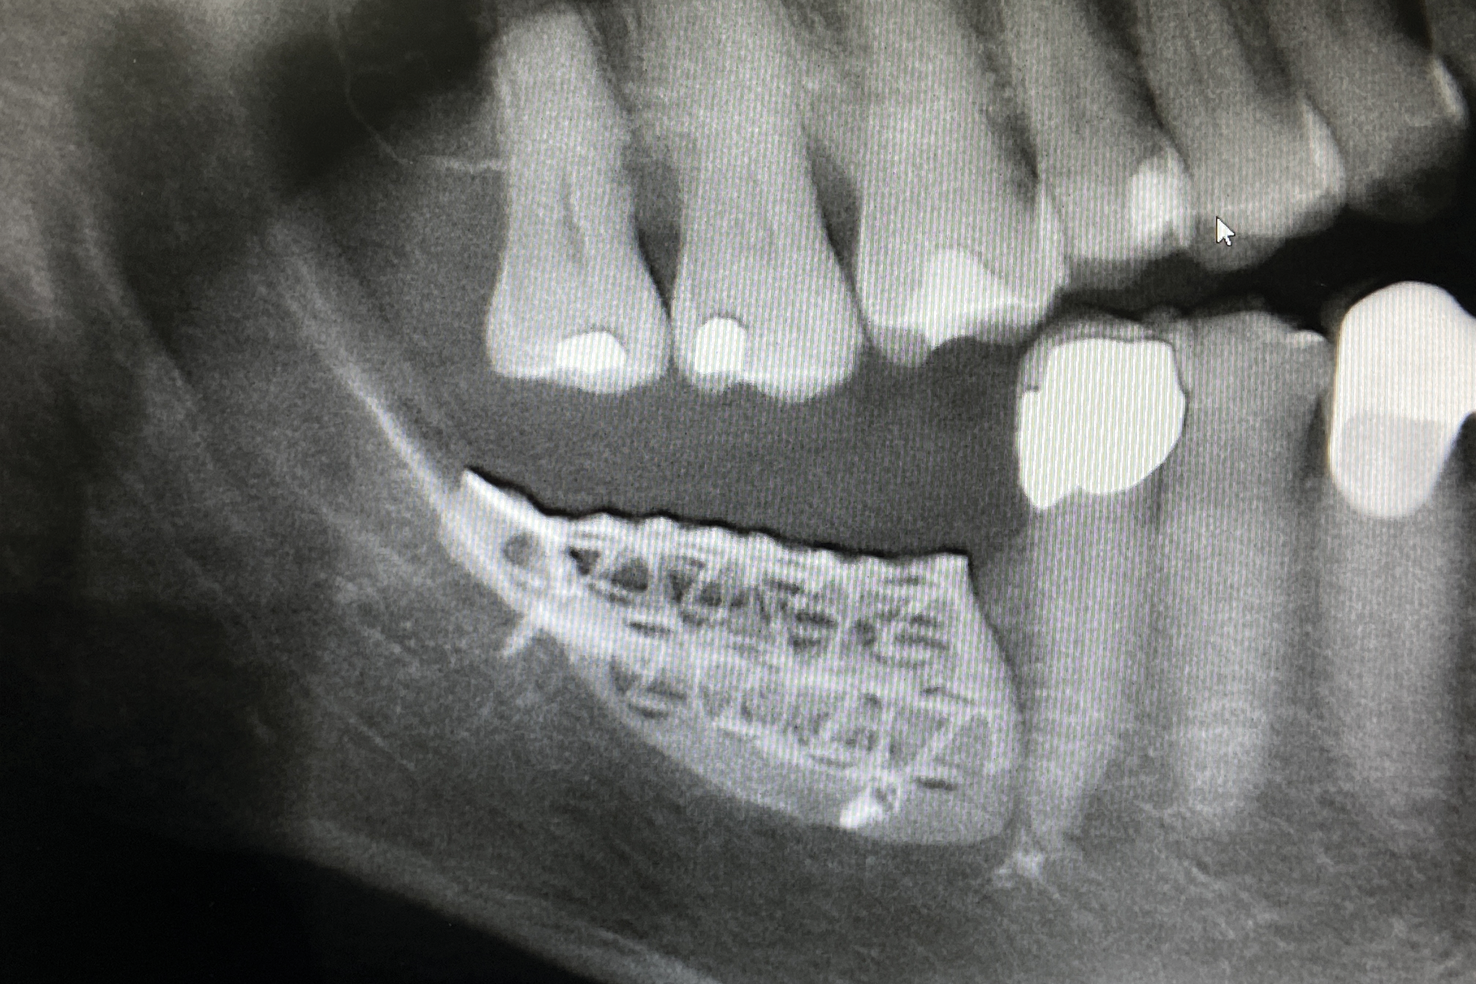

Fig 17. Radiograph after placement of the mesh showing nice seating of the mesh.

Figure 17

Patient 2, a 50-year-old woman with minor osteoporosis, needed grafting because of  severe atrophy in the right mandible (Siebert class II) (Figure 11 and Figure 12). The  titanium mesh mesh was designed using CAD/CAM tech- nology in the same manner as in Case I. In this case, a mix of autologous and xeno- graft was used. Re-entry time was 8 months. The same protocol was followed as in Case 1 (Figure 13 through Figure 17).